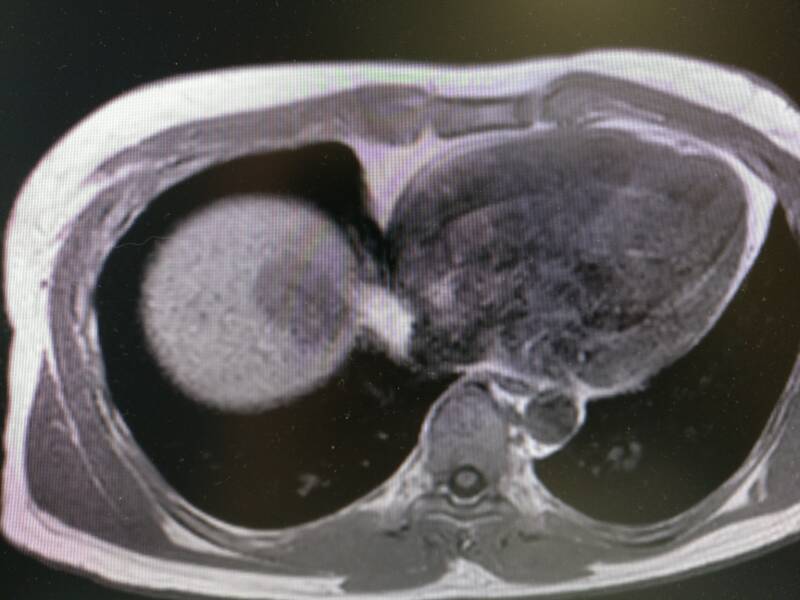

Het plaatje hierboven is een MRI-scan. Hierop kun je de weefsels veel duidelijker zien. Deze MRI is ongeveer dezelfde locatie als de twee bovenstaande plaatjes. Je ziet weer rechts het hart en links de lever. Mijn tumor ziet er nu donkergrijs uit in het lichtere grijs van de lever. In tegenstelling tot een CT-scan, waar die botten wit oplichten, zie je de botstructuur veel minder duidelijk op een MRI. Maar de spieren en de vetlagen onder mijn huid die op de MRI mooi zichtbaar zijn, zijn een grijze brij op de CT.

Als laatste nog twee plaatjes van de MRI scan. Hierop zie je de stappen waarmee de artsen door mijn lichaam kunnen scrollen. We gaan van boven naar onderen. Mijn lever wordt dus steeds groter op de plaatjes omdat die onderin mijn lichaam groter is.